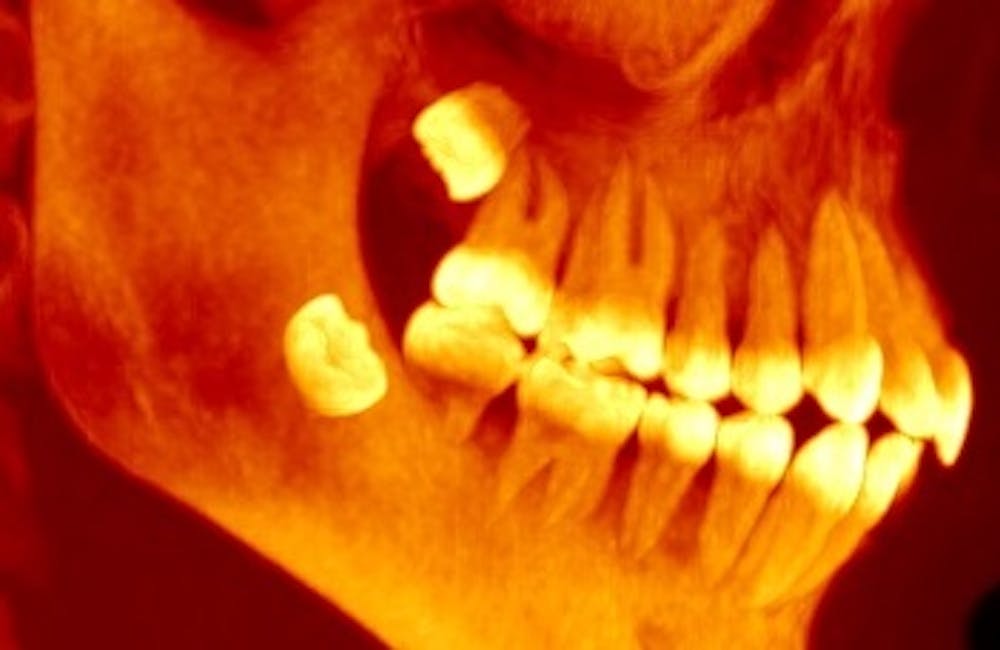

Pada sebagian orang gigi ini kerap tumbuh dengan posisi miring sehingga menimbulkan keluhan sakit. Kenapa tumbuhnya gigi bungsu sakit. Meskipun demikian banyak orang yang memutuskan untuk mencabut gigi bungsu akibat rasa sakit yang ditimbulkan sangat mengganggu ketika hendak melakukan aktivitas sehari hari. Sebagai gigi yang keluar paling akhir terkadang gigi bungsu tidak mendapat ruang yang cukup untuk tumbuh dan keluar dari gusi.

Tapi kebanyakan orang memiliki rahang yang terlalu kecil untuk memungkinkan seluruh 32 gigi muat berjejer di atasnya. Biasanya gigi bungsu ini disebut juga wisdom tooth atau gigi geraham ketiga. Gigi bungsu atau biasa disebut juga dengan gigi geraham tiga adalah gigi yang terakhir yang tumbuh pada kisaran usia 17 25 tahun. Dan jika gigi bungsu ini muncul pada wanita hamil maka tidak boleh dicabut.

Gigi bungsu adalah gigi geraham terakhir yang terletak paling belakanggigi geraham bungsu umumnya tumbuh ketika seseorang menginjak usia remaja atau dewasa yaitu sekitar usia 1725 tahun. Halodoc jakarta gigi bungsu merupakan gigi yang akan mengalami pertumbuhan pada saat seseorang berusia 17 tahun ke atasgigi ini biasanya akan tumbuh dengan disertai rasa sakit yang akan mengganggu aktivitas harian seperti makan dan berbicara.